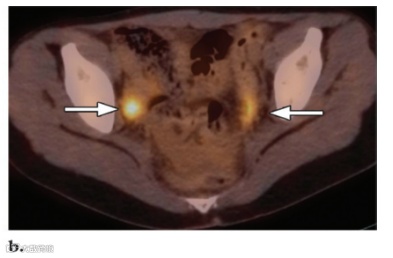

图13. 一名17岁女孩的卵巢黄体囊肿,该女孩有IVB期霍奇金病病史。患者最近一次月经发生在完成化疗后接受FDG PET/CT 随访前3周。

(a)冠状FDG PET 扫描显示骨盆右侧局部摄取增加(箭头)。

(b)横向CT扫描显示右卵巢有囊性结构,边缘增强(箭头),这一发现与卵巢黄体囊肿一致。

(c)横向融合PET/CT图像显示囊肿局部摄取增加(箭头)。